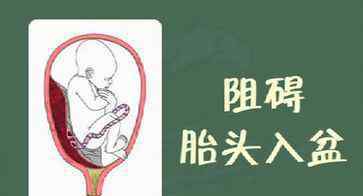

盆腔狭窄、前置胎盘、巨大胎儿等。

比如我们可能听说过“前置胎盘”这种病,就是胎盘比较低,位于子宫较低的位置。由于胎盘在盆腔内占有一定的距离空,会阻碍胎头正常进入盆腔。这时,胎头会向其他方向转动,造成臀位或横位等胎位异常。